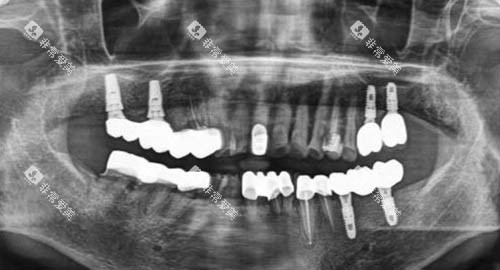

上海美田口腔门诊部的诊疗科目涵盖种植修复、牙齿矫正、牙周治疗等 11 个科室,能够满足不同患者的口腔诊疗需求。

门诊部拥有 1100 平方米的独立医疗空间,配备了 15 间标准诊室以及符合院感要求的独立种植手术室。

医疗器械均持有医疗器械注册证,让患者可以放心就诊。